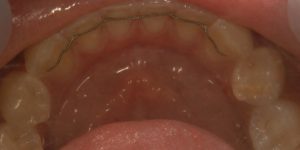

ワイヤー保定

当院の場合ですと、矯正治療後しばらくは保定をワイヤーのみで行うことはあまりなく、ほとんどがマウスピースとの併用になります。日中はこれだけ、寝るときには保定用マウスピースもつけていただくというW保定が多いです。

完全に歯に接着するため、マウスピースをしていなくても前歯が動かないのは安心ですが、フロスが通らなくなるので、お手入れがややしにくいかもしれません。

たとえば、日中はできればマウスピースを外して過ごしたい、またはお仕事上制約が多くあまり長時間つけられない方や、元々の歯並びがかなり凸凹が大きかった、すきっ歯、八重歯。。など歯の状態によってマウスピースだけだと保定力が不十分な場合にもワイヤー保定を行います。